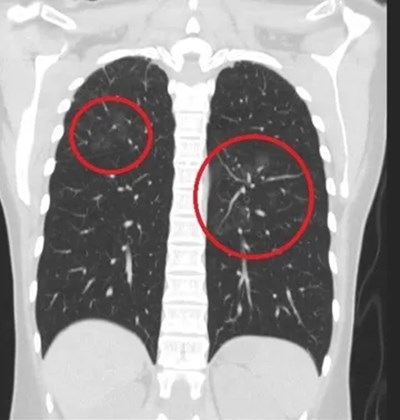

วันที่ 24 กรกฎาคม 2568 เว็บไซต์ Sin Chew เผยเรื่องราวเกี่ยวกับเคสคนไข้หญิงรายหนึ่งในไต้หวัน เธอเป็นคุณครูอนุบาลวัย 30 ปี ซึ่งไม่มีพฤติกรรมสูบบุหรี่หรือมีอาการไอ แต่กลับตรวจสอบความผิดปกติที่น่าตกใจ มีก้อนเนื้อกระจายอยู่ทั่วในปอดนับสิบจุด ก่อนที่สาเหตุจะถูกเปิดเผยว่า เกิดจากกิจวัตรที่คาดไม่ถึงในห้องเรียน

ซูอี้เฟิง แพทย์ผู้เชี่ยวชาญด้านโรคปอดและทรวงอกในไต้หวัน ได้โพสต์แชร์เรื่องราวนี้ผ่านทางโซเชียลมีเดียเมื่อวันที่ 23 กรกฎาคม ที่ผ่านมา เผยว่า ครูสาวรายนี้ได้ไปที่โรงพยาบาลขนาดใหญ่แห่งหนึ่งเพื่อตรวจสุขภาพ รวมถึงเข้ารับการตรวจคัดกรองมะเร็งปอดด้วย Low-dose CT scan หรือการตรวจเอกซเรย์คอมพิวเตอร์แบบใช้ปริมาณรังสีต่ำ

กระทั่งผลปรากฏว่า พบก้อนเนื้อในปอดที่มีลักษณะขุ่นมัวคล้ายฝ้ากระจก เป็นจำนวนมากกว่า 10 ตำแหน่ง และบางตำแหน่งมีขนาดใหญ่กว่า 1 เซนติเมตร หลังจากแพทย์ซักถามประวัติคนไข้โดยละเอียด ทำให้ทราบว่า เธอจำเป็นต้องใช้น้ำยาฟอกขาวสำหรับฆ่าเชื้อเป็นประจำในห้องเรียน แพทย์จึงวินิจฉัยว่า เธอเป็นโรคปอดอักเสบจากสารเคมี ปอดอักเสบที่เกิดจากการสูดดมน้ำยาฟอกขาว ไม่ใช่ก้อนเนื้อในปอดที่เกิดจากมะเร็ง